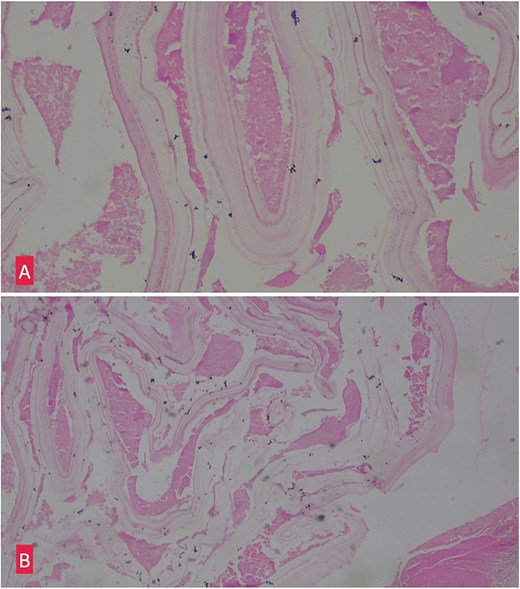

(A) Hemotoxylin and eosin ×10: Section shows lamellated appearance of hydatid cyst. (B) Hemotoxylin and eosin ×40: Section shows lamellated appearance of hydatid cyst.

Histopathological examination of the excised cyst wall confirmed the diagnosis, showing a lamellated membrane (Fig. 3).